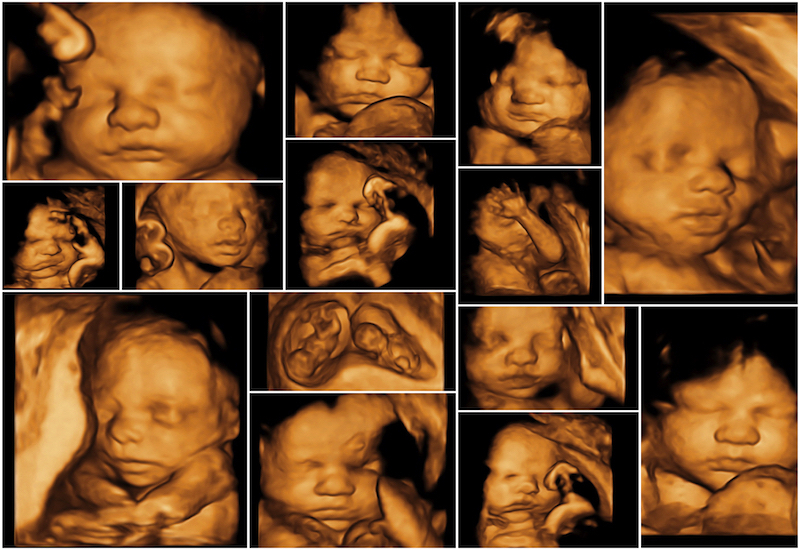

Siêu âm 4D

Siêu âm 4D hay siêu âm bốn chiều về cơ bản là giống siêu âm 3D nhưng khác biệt ở chỗ có thể cung cấp video chuyển động của thai nhi trong thời gian thực. Giống như siêu âm 3D, siêu âm 4D cũng cho phép bác sĩ chẩn đoán các vấn đề sức khỏe của thai nhi dựa trên hình ảnh siêu âm rõ nét hơn so với hình ảnh 2D. Nói cách khác, siêu âm 4D chính là siêu âm 3D chuyển động.

Sieu-am-4D Hình ảnh siêu âm 3D, 4D